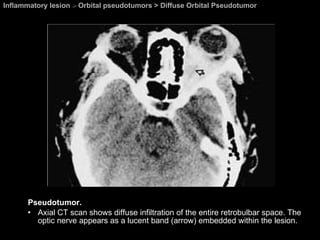

Diffuse Orbital Pseudotumor Orbital pseudotumors  Tumefactive, or infiltrative type of pseudotumor Entire retrobulbar space and mold itself around the globe while respecting its natural shape.  These large, bulky masses can be intraconal, extraconal, or involve both spaces.  Very difficult to differentiate from lymphoma.

Inflammatory lesion  >  Orbital pseudotumors > Diffuse Orbital Pseudotumor Pseudotumor. Axial CT scan shows diffuse infiltration of the entire retrobulbar space. The optic nerve appears as a lucent band (arrow) embedded within the lesion.